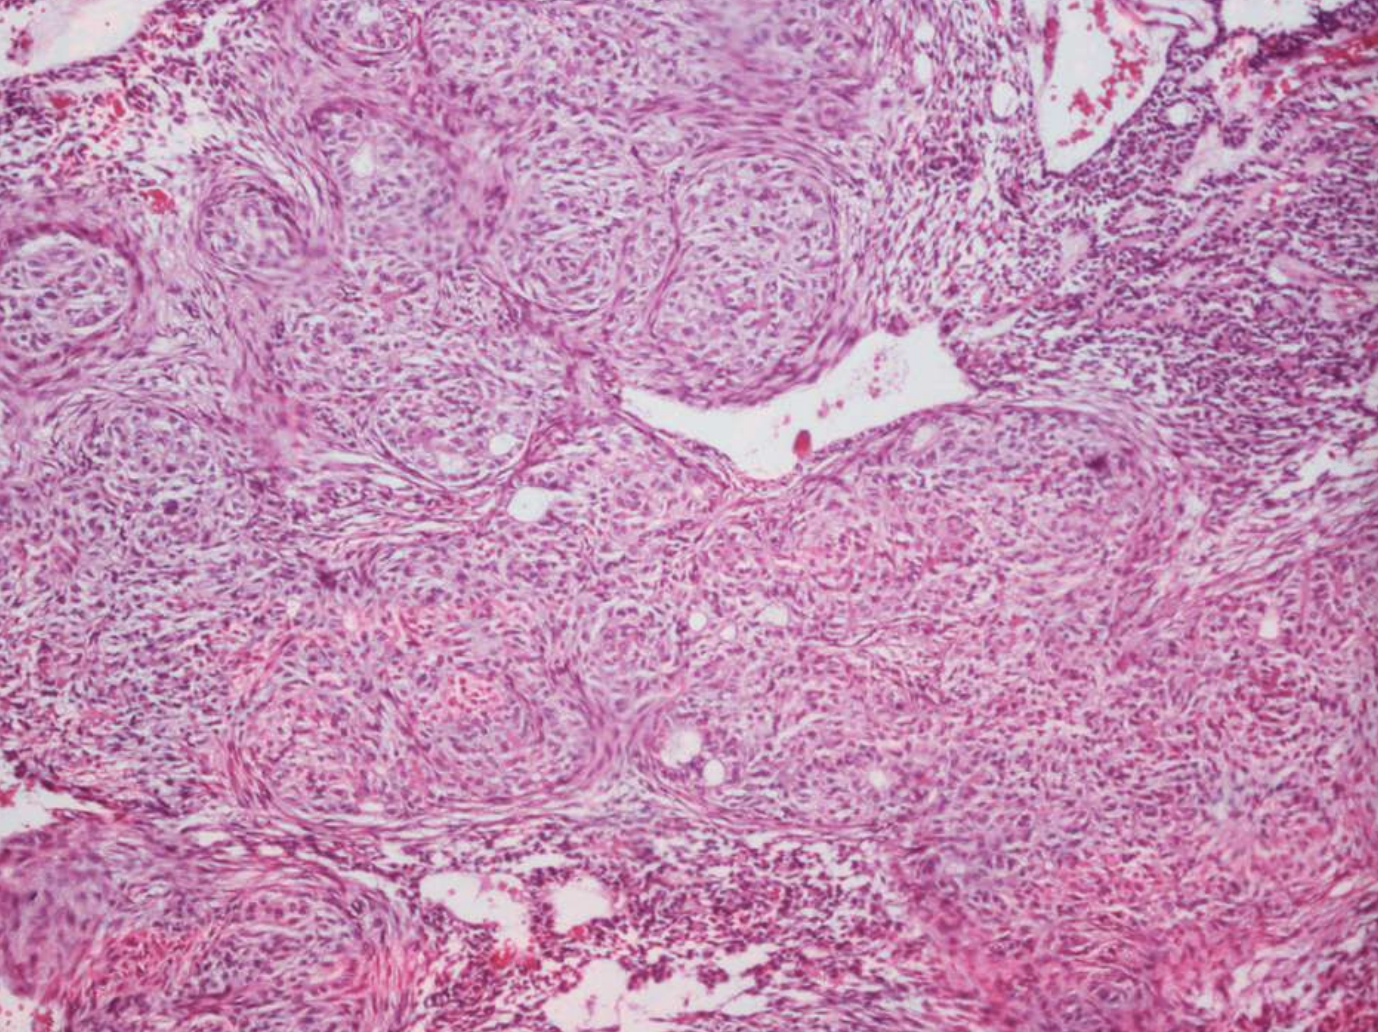

what are histopathologic patterns of ameloblastomas?

• Follicular

• Plexiform

• Acanthomatous

• Granular cell

• Basal cell

• Desmoplastic

what are the key microscopic histopathologic appearance of ameloblastomas?

Follicular pattern

Nests of epithelium

Island centers resembling stellate reticulum

Peripheral columnar cells with nuclei polarized opposite basement membrane (sub-nuclear vacuolization)

Mature fibrous background

Desmoplastic pattern

Compressed islands and cords of odontogenic epithelium in densely collagenized stroma

ameloblastoma (Island centers resembling stellate reticulum)